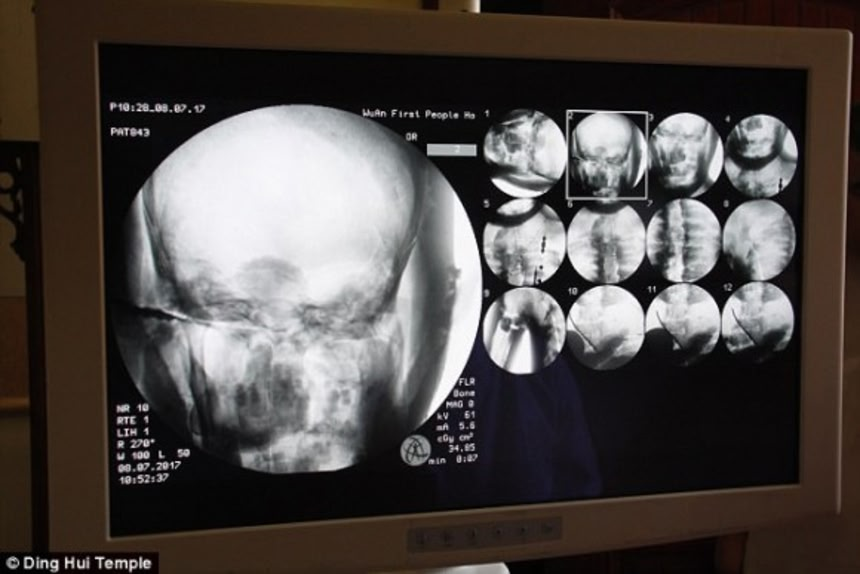

数年前、オランダ・ドレンテ博物館が所有する仏像をCTスキャンしたところ、ミイラになった即身仏が中に入っていたことが話題となったが(関連記事)、中国河北省武安市の定慧寺に納められている、金メッキを施された慈賢法師の仏像をCTスキャンしたところ、健康な骨と完全な脳が残されていることが明らかとなった。

7月8日に行われたCTの調査は僧侶、メディア、信者らの立会いのもと行われた。慈賢法師に完全な骨格と完全な脳がまだ存在することが明らかになり、人々は衝撃を受けたようだ。

この画像を大きなサイズで見るスキャンを行なった後、武永庆博士は「骨は普通の人と同じくらい健康に見えますね」とコメント。「上顎、上歯、肋骨、脊髄、すべての関節まで、どれも完全です。まったく驚きですよ」

スキャンを行なった後、武永庆 博士は「骨は普通の人と同じくらい健康に見えますね」とコメント

「上顎、上歯、肋骨、脊髄、 すべての関節、心臓の動きまで、どれも完全です。まったく驚きですよ」

ともコメント